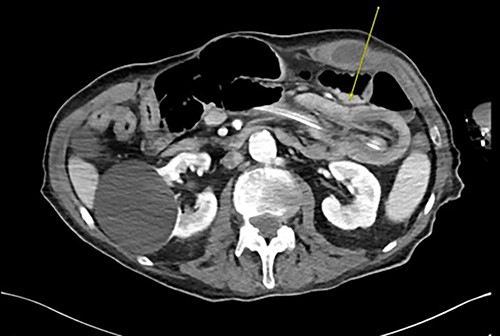

Three weeks later, he presented with a JT obstruction. Multiple attempts using carbonated fluids, enzymes and mechanical brushing failed to clear the obstruction. A computerized tomography of the abdomen and pelvis (CTAP) confirmed the position of the JT and demonstrated telescoping of a long 17 cm segment of jejunum starting from the tip of the JT as lead point (Fig. 1). The JT was removed in hopes of resolution. However, repeat CTAP showed persistent intussusception with mesenteric fat stranding, and possible intestinal ischemia (Fig. 2).

Repeat CTAP s/p JT removal revealed persistent J–J intussusception (yellow arrow).